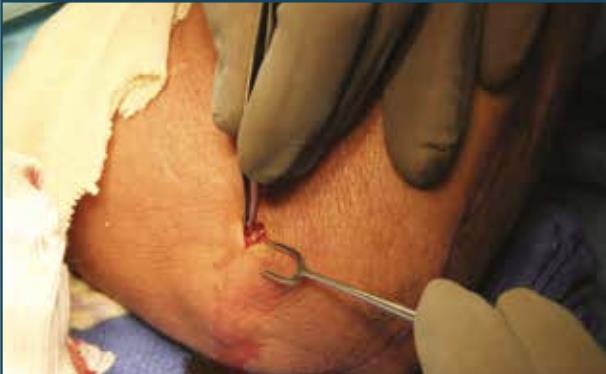

• Guide wire attachment

• insert the K-wire Guide into the Axis Guide so that it is close to the lateral epicondyle without making contact, and then rotate it clockwise to lock it in place

• Guide wire insertion

• advance the Guide-Wire (1.5mm K-wire) through the K-wire Guide and into the humerus, stopping short of the medial cortex

• caution

• DO NOT violate the medial cortex as it may result in ulnar nerve injury